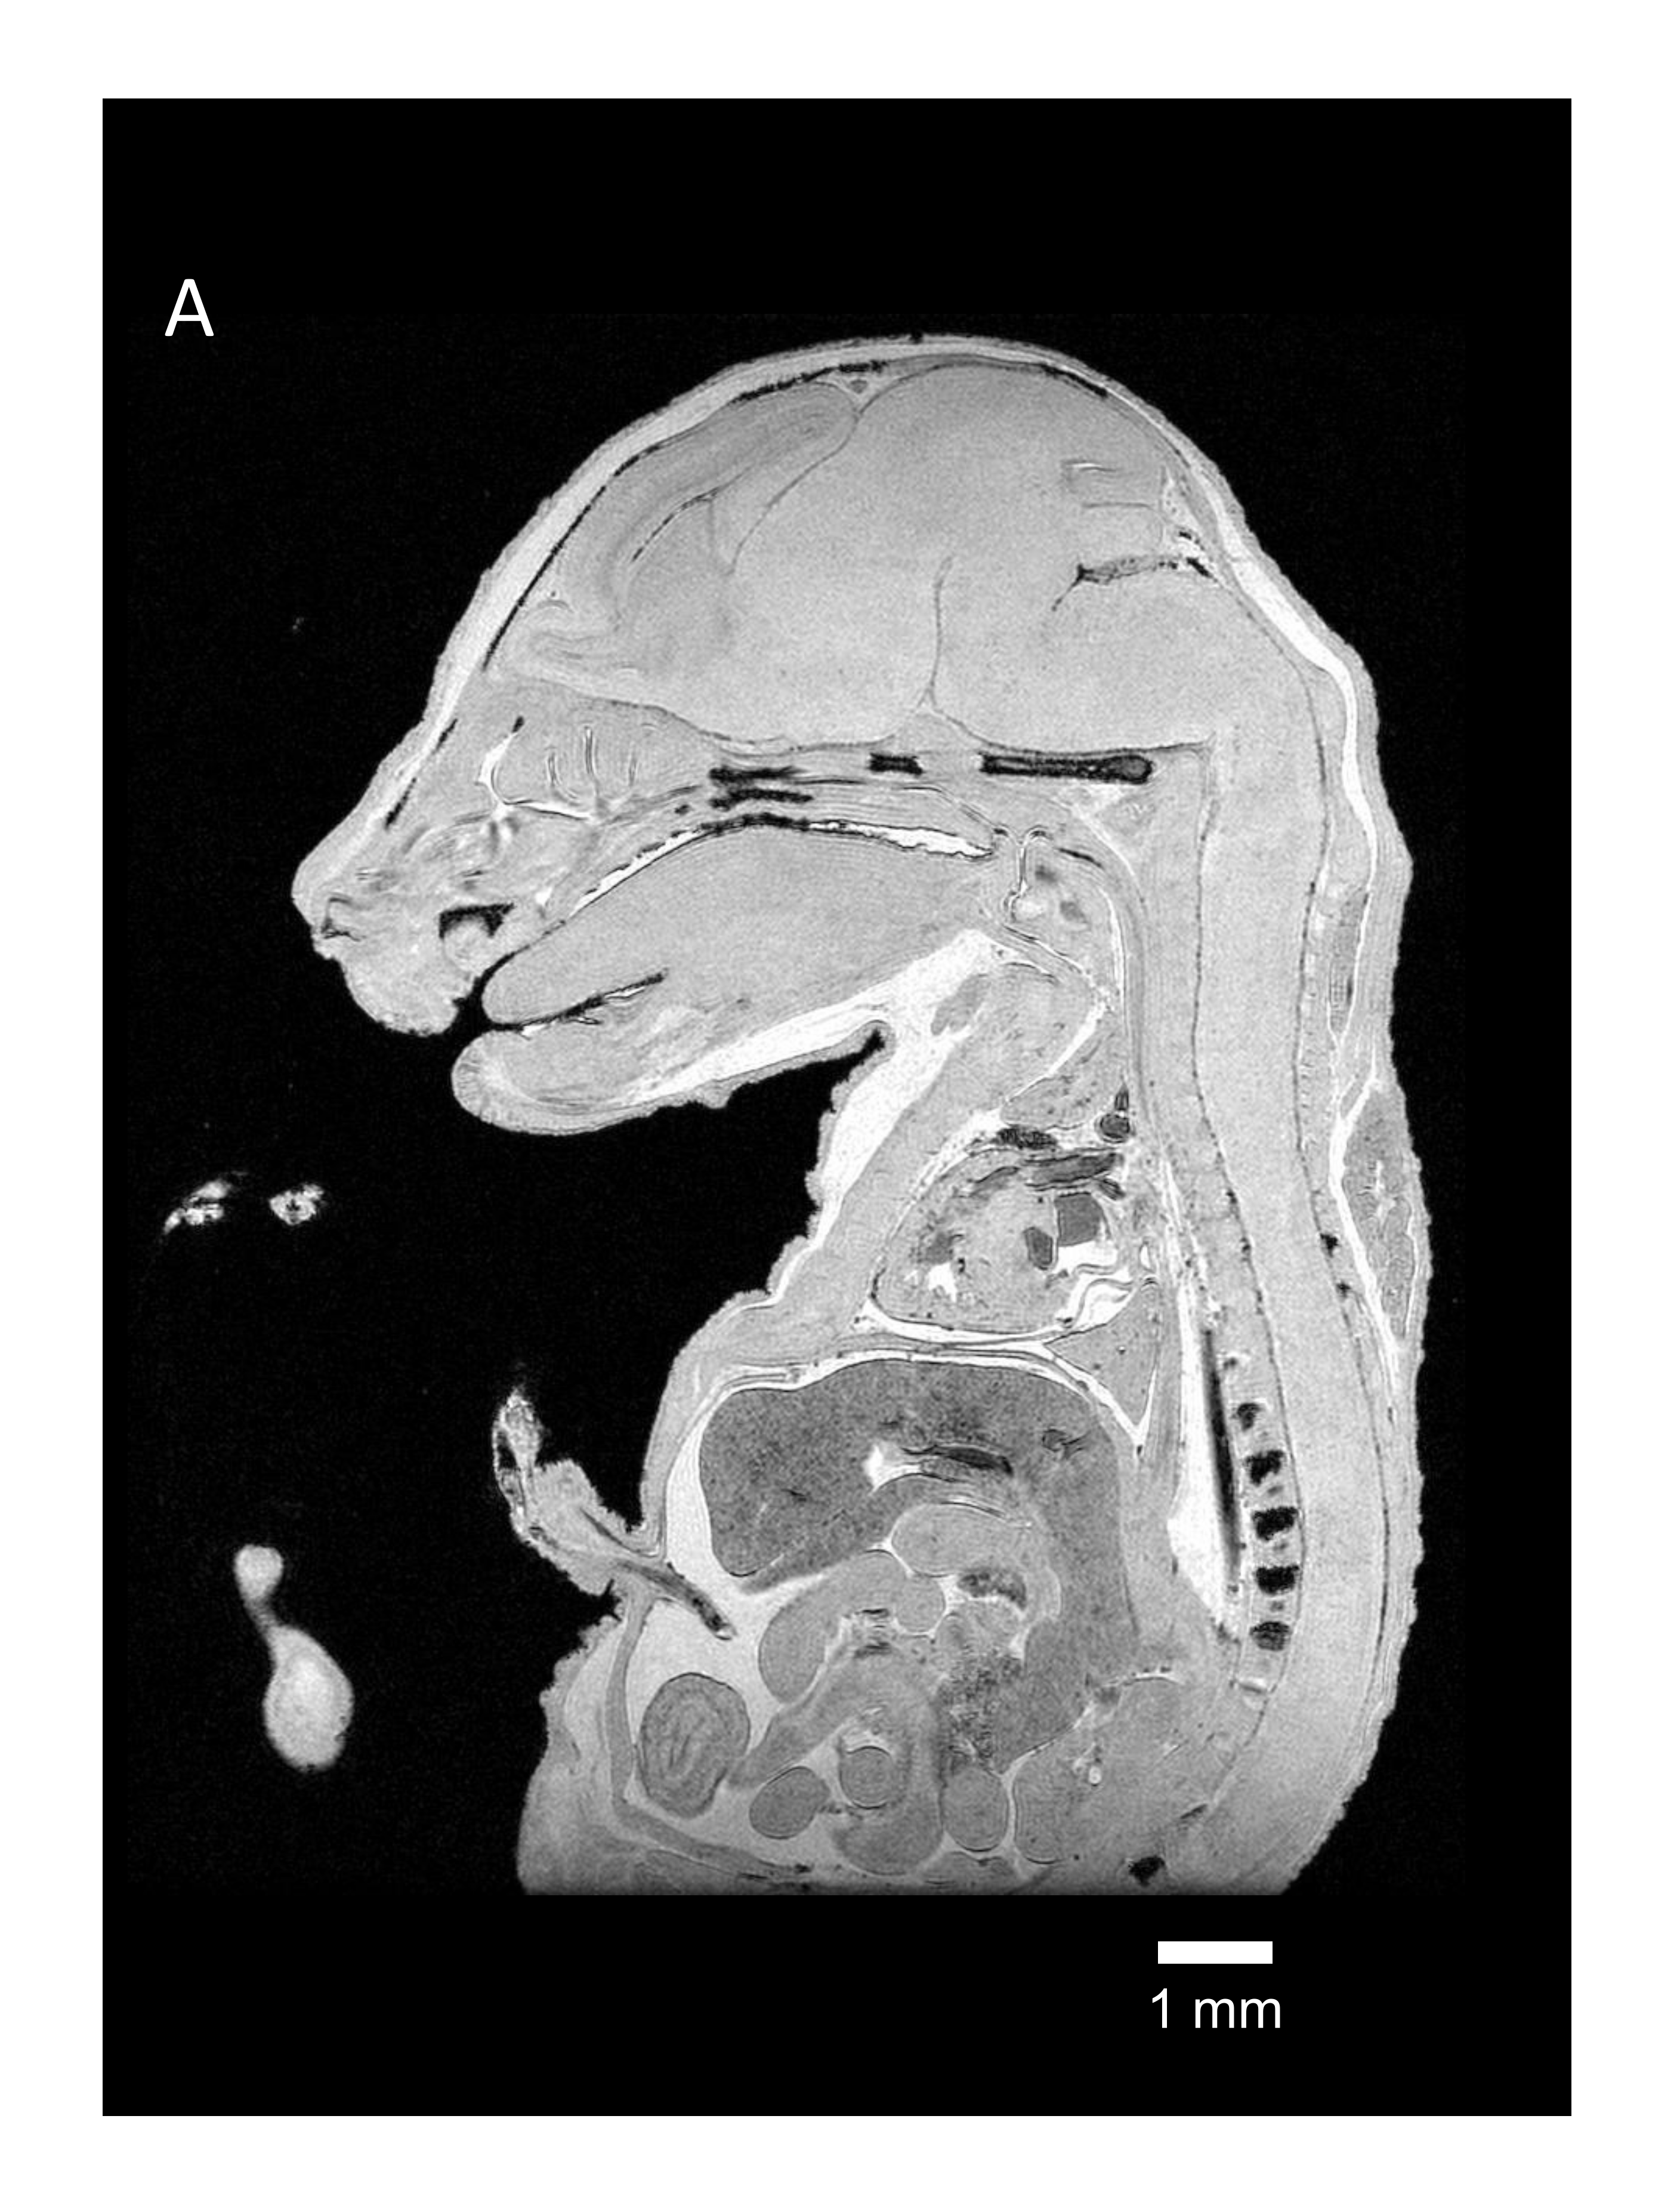

Figure 2 Ultrahigh-resolution image of mouse embryo with Gd-PS-PBS.